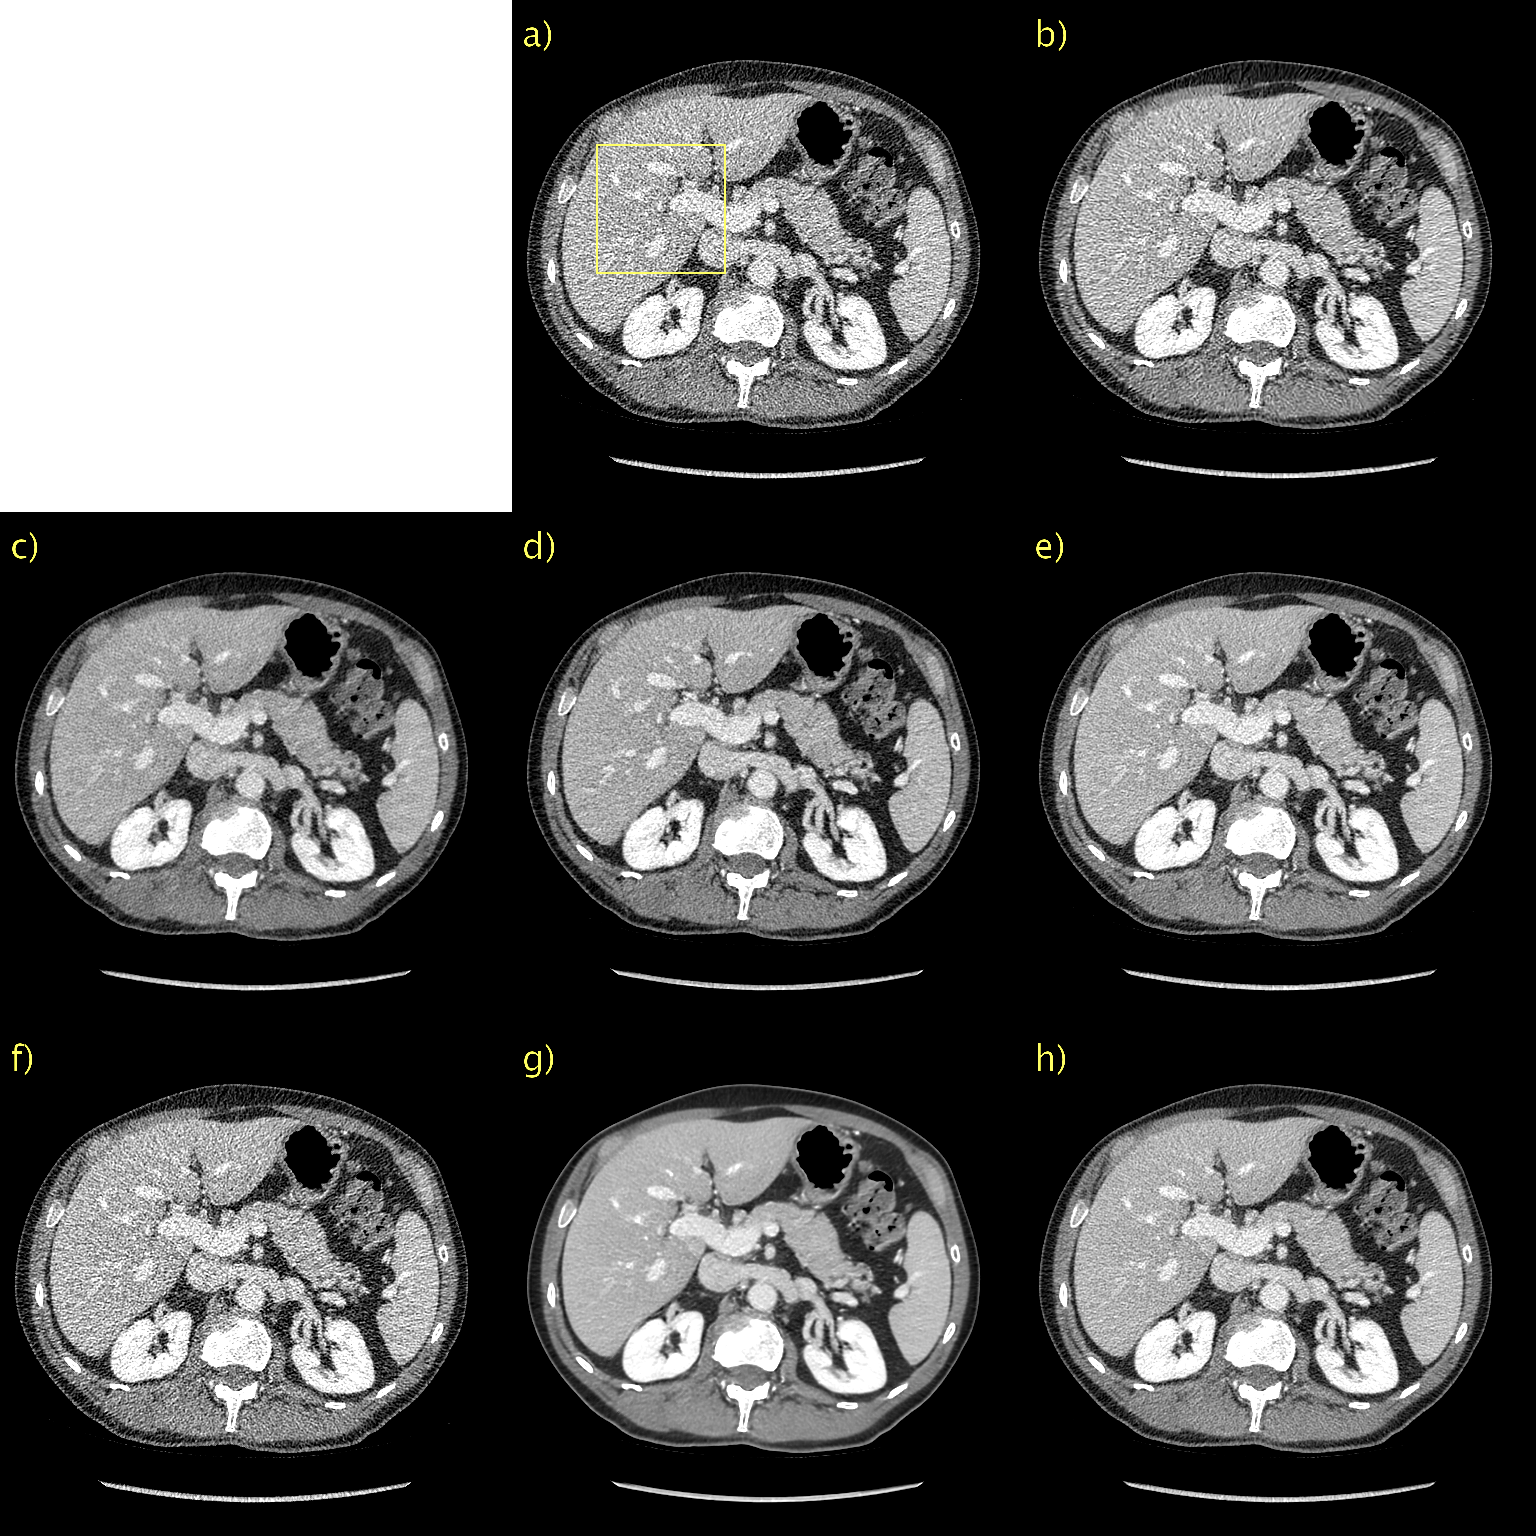

Qualitative results for a representative slice in the first PCCT test case appear in Fig. 4 with a magnification of the indicated ROI in Fig. 5. Due to the lack of “ground truth” images, we resort to qualitative evaluation. It is also difficult to discriminate signal from noise when it comes to fairly small and low-contrast details. We simply define good performance as accurately reproducing the unprocessed image, shown in a), but with a lower noise level. BM3D, in b), seems to generalize poorly from the low-dose CT data. This is likely due to difference in noise characteristics; one would need to re-estimate σBM3D.subscript𝜎BM3D\sigma_{\text{BM3D}}. All other methods seem to generalize well in the sense that there are no major changes in performance. There is a significant performance gain for proposed method with D=128𝐷128D=128 compared to D.𝐷D\rightarrow\infty. This is most visible in the magnified ROI in Fig. 7 as D𝐷D\rightarrow\infty, shown in g), is significantly more blurry than D=128,𝐷128D=128, shown in h). We have overlaid a yellow arrow, indicating a detail of interest. Since we do not have a ground truth, and we are considering a single slice, we cannot definitively state that this is not just a noise spike. However, since it is clearly visible in the unprocessed image, we want it to be visible in the processed images as well. As we can see, this is indeed the case with the notable exception of CD, shown in d). Moreover, the contrast of this detail appears to vary, and seems to be much more well defined for the proposed with D=128𝐷128D=128 than for WGAN-VGG, shown in c). Hence, it appears than the proposed method, despite being unsupervised, is able to perform very competitively even compared to supervised methods such as WGAN-VGG and CD.

Figure 4: Results for first PCCT test case. a) Unprocessed, b) BM3D, c) WGAN-VGG, d) CD, e) PPFM, f) Noise2Void g) D𝐷D\rightarrow\infty h) D=128𝐷128D=128. No ground truth available. Yellow box indicating ROI shown in Fig. 5. 0.42 mm-slices. Window setting [-160,240] HU.

Figure 5: ROI in Fig. 4 magnified to emphasize details. a) Unprocessed, b) BM3D, c) WGAN-VGG, d) CD, e) PPFM, f) Noise2Void g) D𝐷D\rightarrow\infty h) D=128𝐷128D=128. No ground truth available. Yellow arrow placed to emphasize detail. 0.42 mm-slices. Window setting [-160,240] HU.

Results for a representative slice in the second PCCT test are shown in Fig. 6 and Fig. 7. Again, no “ground truth” is available. BM3D, in b), seems to perform better than for the first PCCT test case. The denoising performance is now more aligned with what was observed for the low-dose CT validation data. The difference in performance is likely due to differences in noise characteristics and lack of generalization. Lack of generalization does not seem to be an issue for any other method as performance is very consistent across the validation and test data. We have again placed a yellow arrow to indicate details of interest, in this case fat in the back muscle. Contrast is difficult to assess qualitatively when comparing proposed with D𝐷D\rightarrow\infty, shown in g), and D=128𝐷128D=128, shown in h), due to the large difference in noise level. D𝐷D\rightarrow\infty is definitely over-smoothed and thus more blurry; however, the contrast of this particular detail seem to be fairly well preserved. The proposed method with D=128𝐷128D=128 again performs very competitively compared to WGAN-VGG, shown in c), as can be seen when considering the contrast of fat and muscle.

Figure 6: Results for second PCCT test case. a) Unprocessed, b) BM3D, c) WGAN-VGG, d) CD, e) PPFM, f) Noise2Void g) D𝐷D\rightarrow\infty h) D=128𝐷128D=128. No ground truth available. Yellow box indicating ROI shown in Fig. 7. 0.42 mm-slices. Window setting [-160,240] HU.

Figure 7: ROI in Fig. 6 magnified to emphasize details. a) Unprocessed, b) BM3D, c) WGAN-VGG, d) CD, e) PPFM, f) Noise2Void g) D𝐷D\rightarrow\infty h) D=128𝐷128D=128. No ground truth available. Yellow arrow placed to emphasize detail. 0.42 mm-slices. Window setting [-160,240] HU.